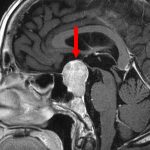

症例 '25年5月

No.

631

’25_33

'25年5月

60代

下垂体腺腫

頭蓋内腫瘍摘出術

断層撮影

手術前

1

手術前2

手術後